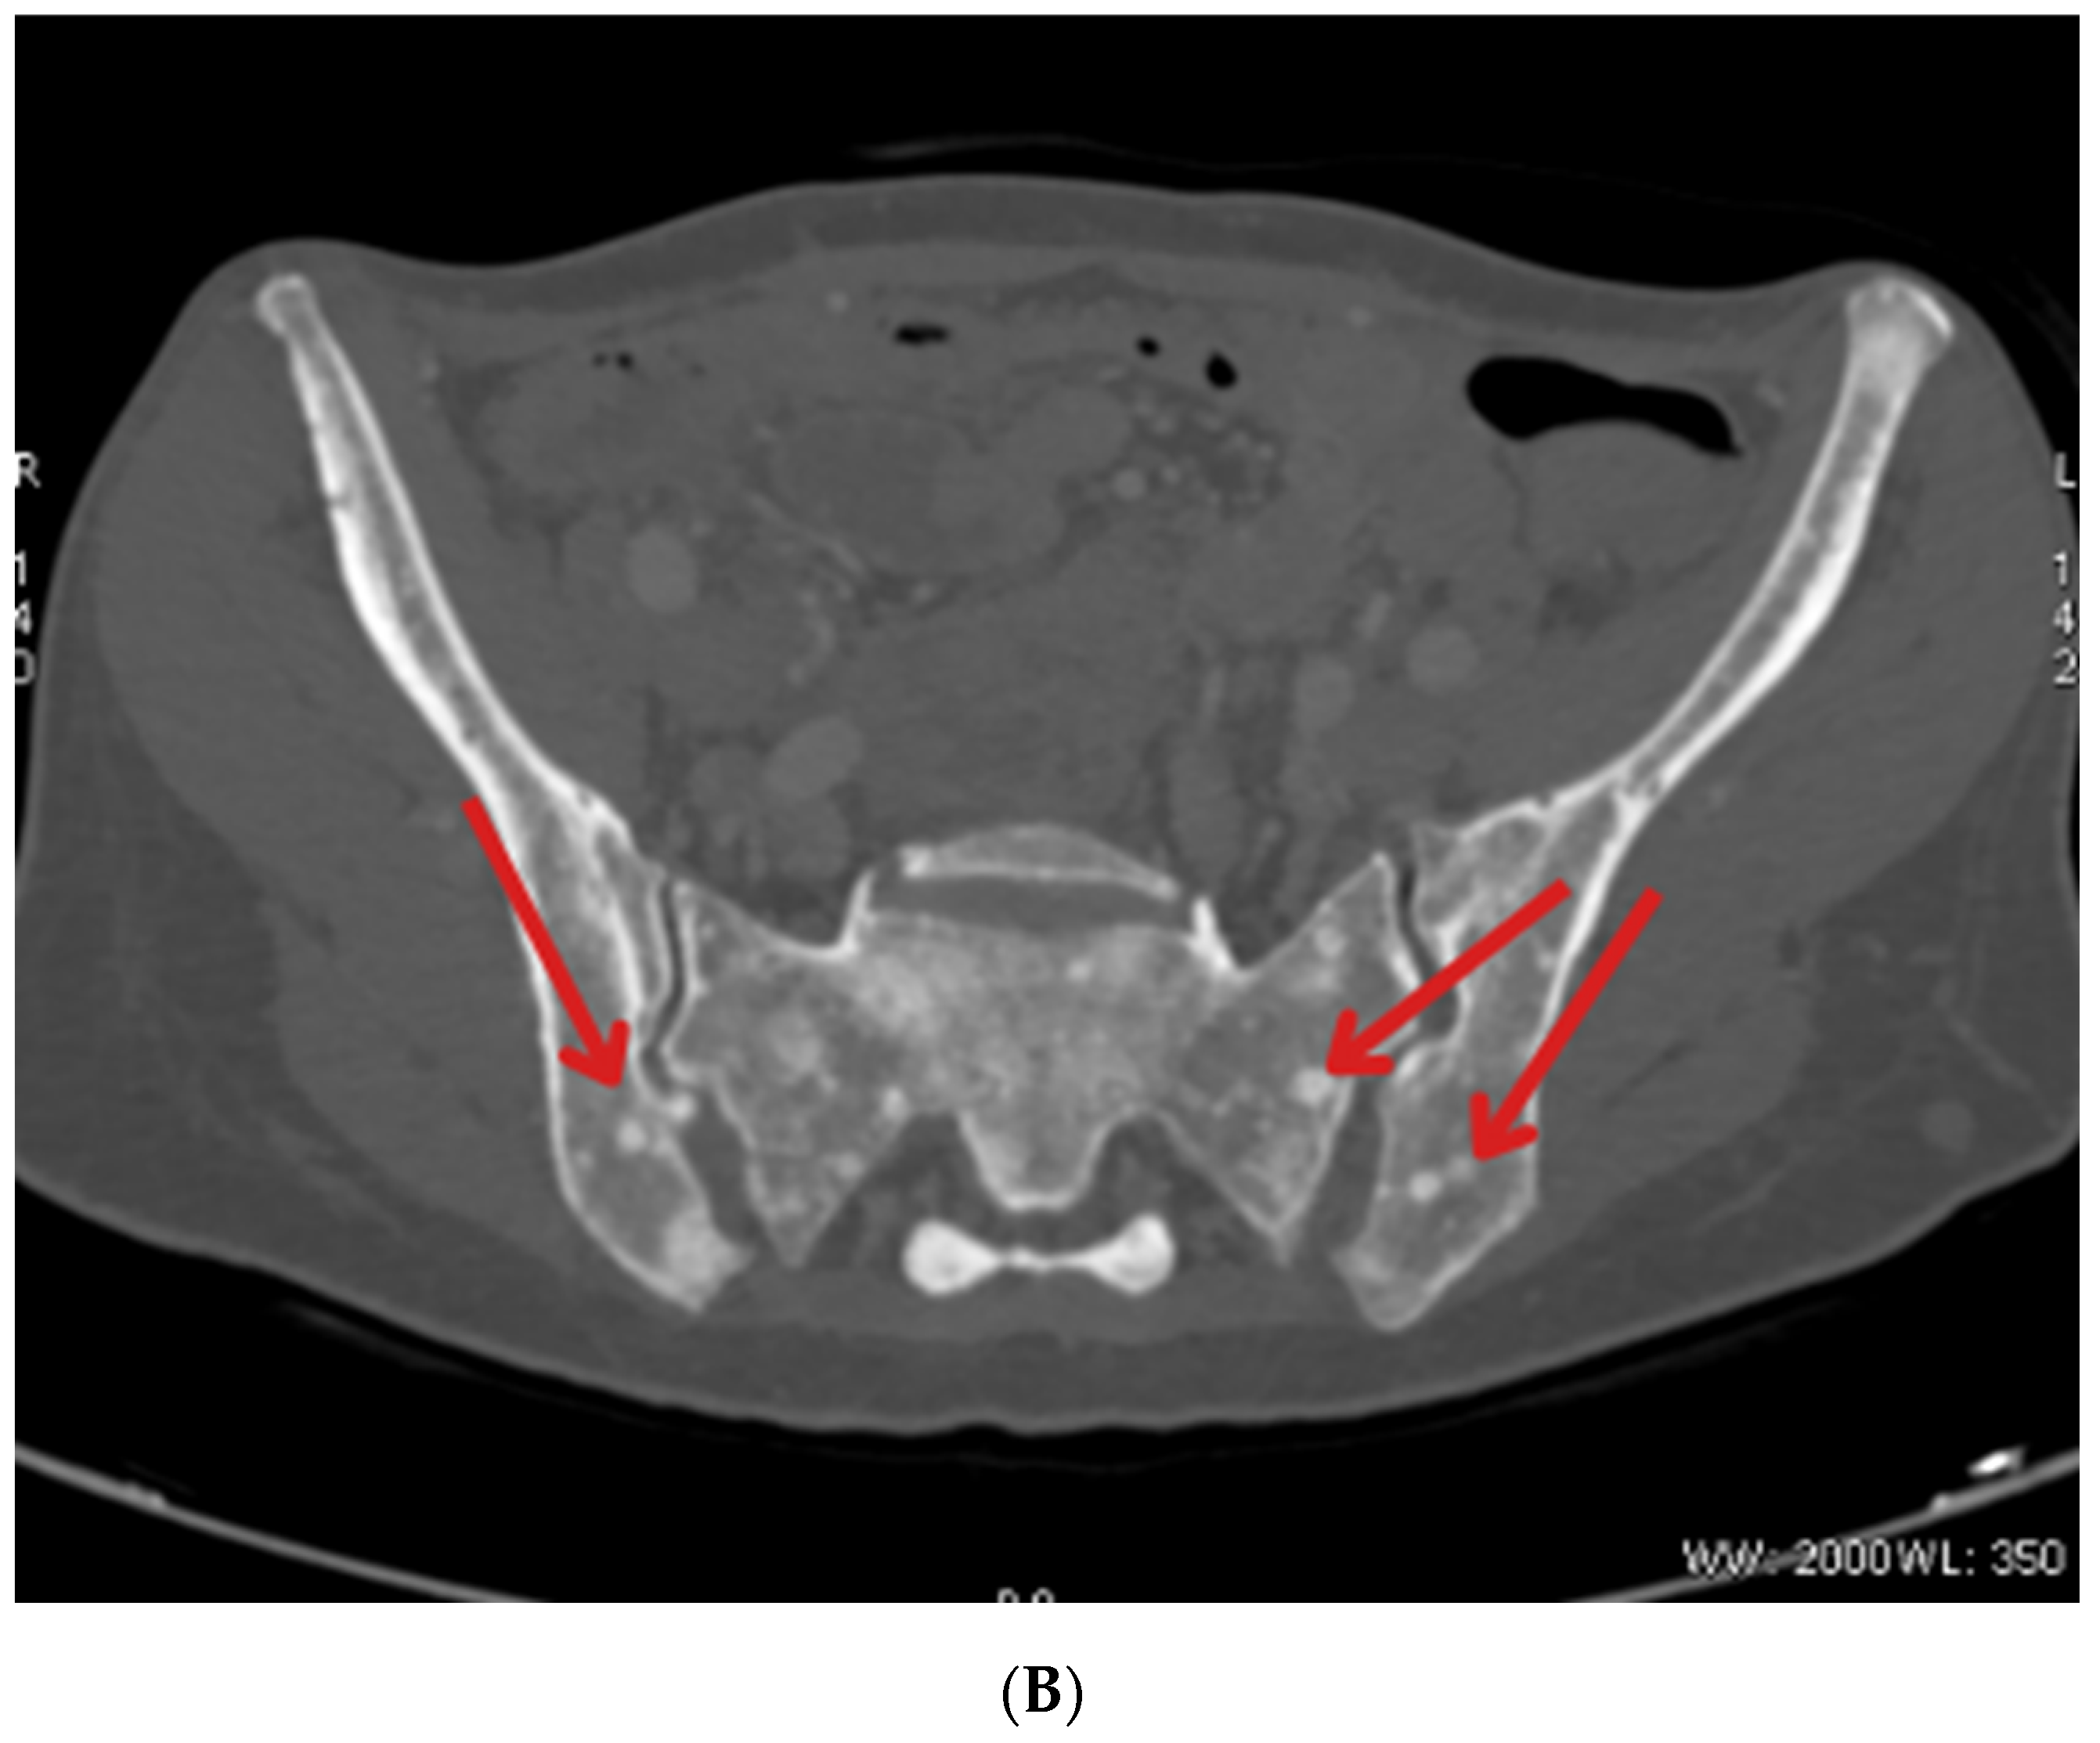

| May 2023 | Beginning of Lutathera treatment CT scan: metastases in the liver, bone sclerosis, enlarged lymph nodes |

| October 2023 | Significant progression of metastases in the liver and bones (spine, ribs, pelvis), and periaortic and pelvic lymphadenopathy The patient was referred to palliative hospice care, resigned from further PRPRT treatment |